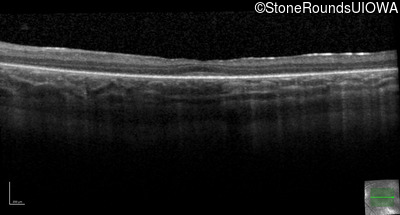

Optical Coherence Tomography - Left - 20/80

Exemplar / OCT Stack